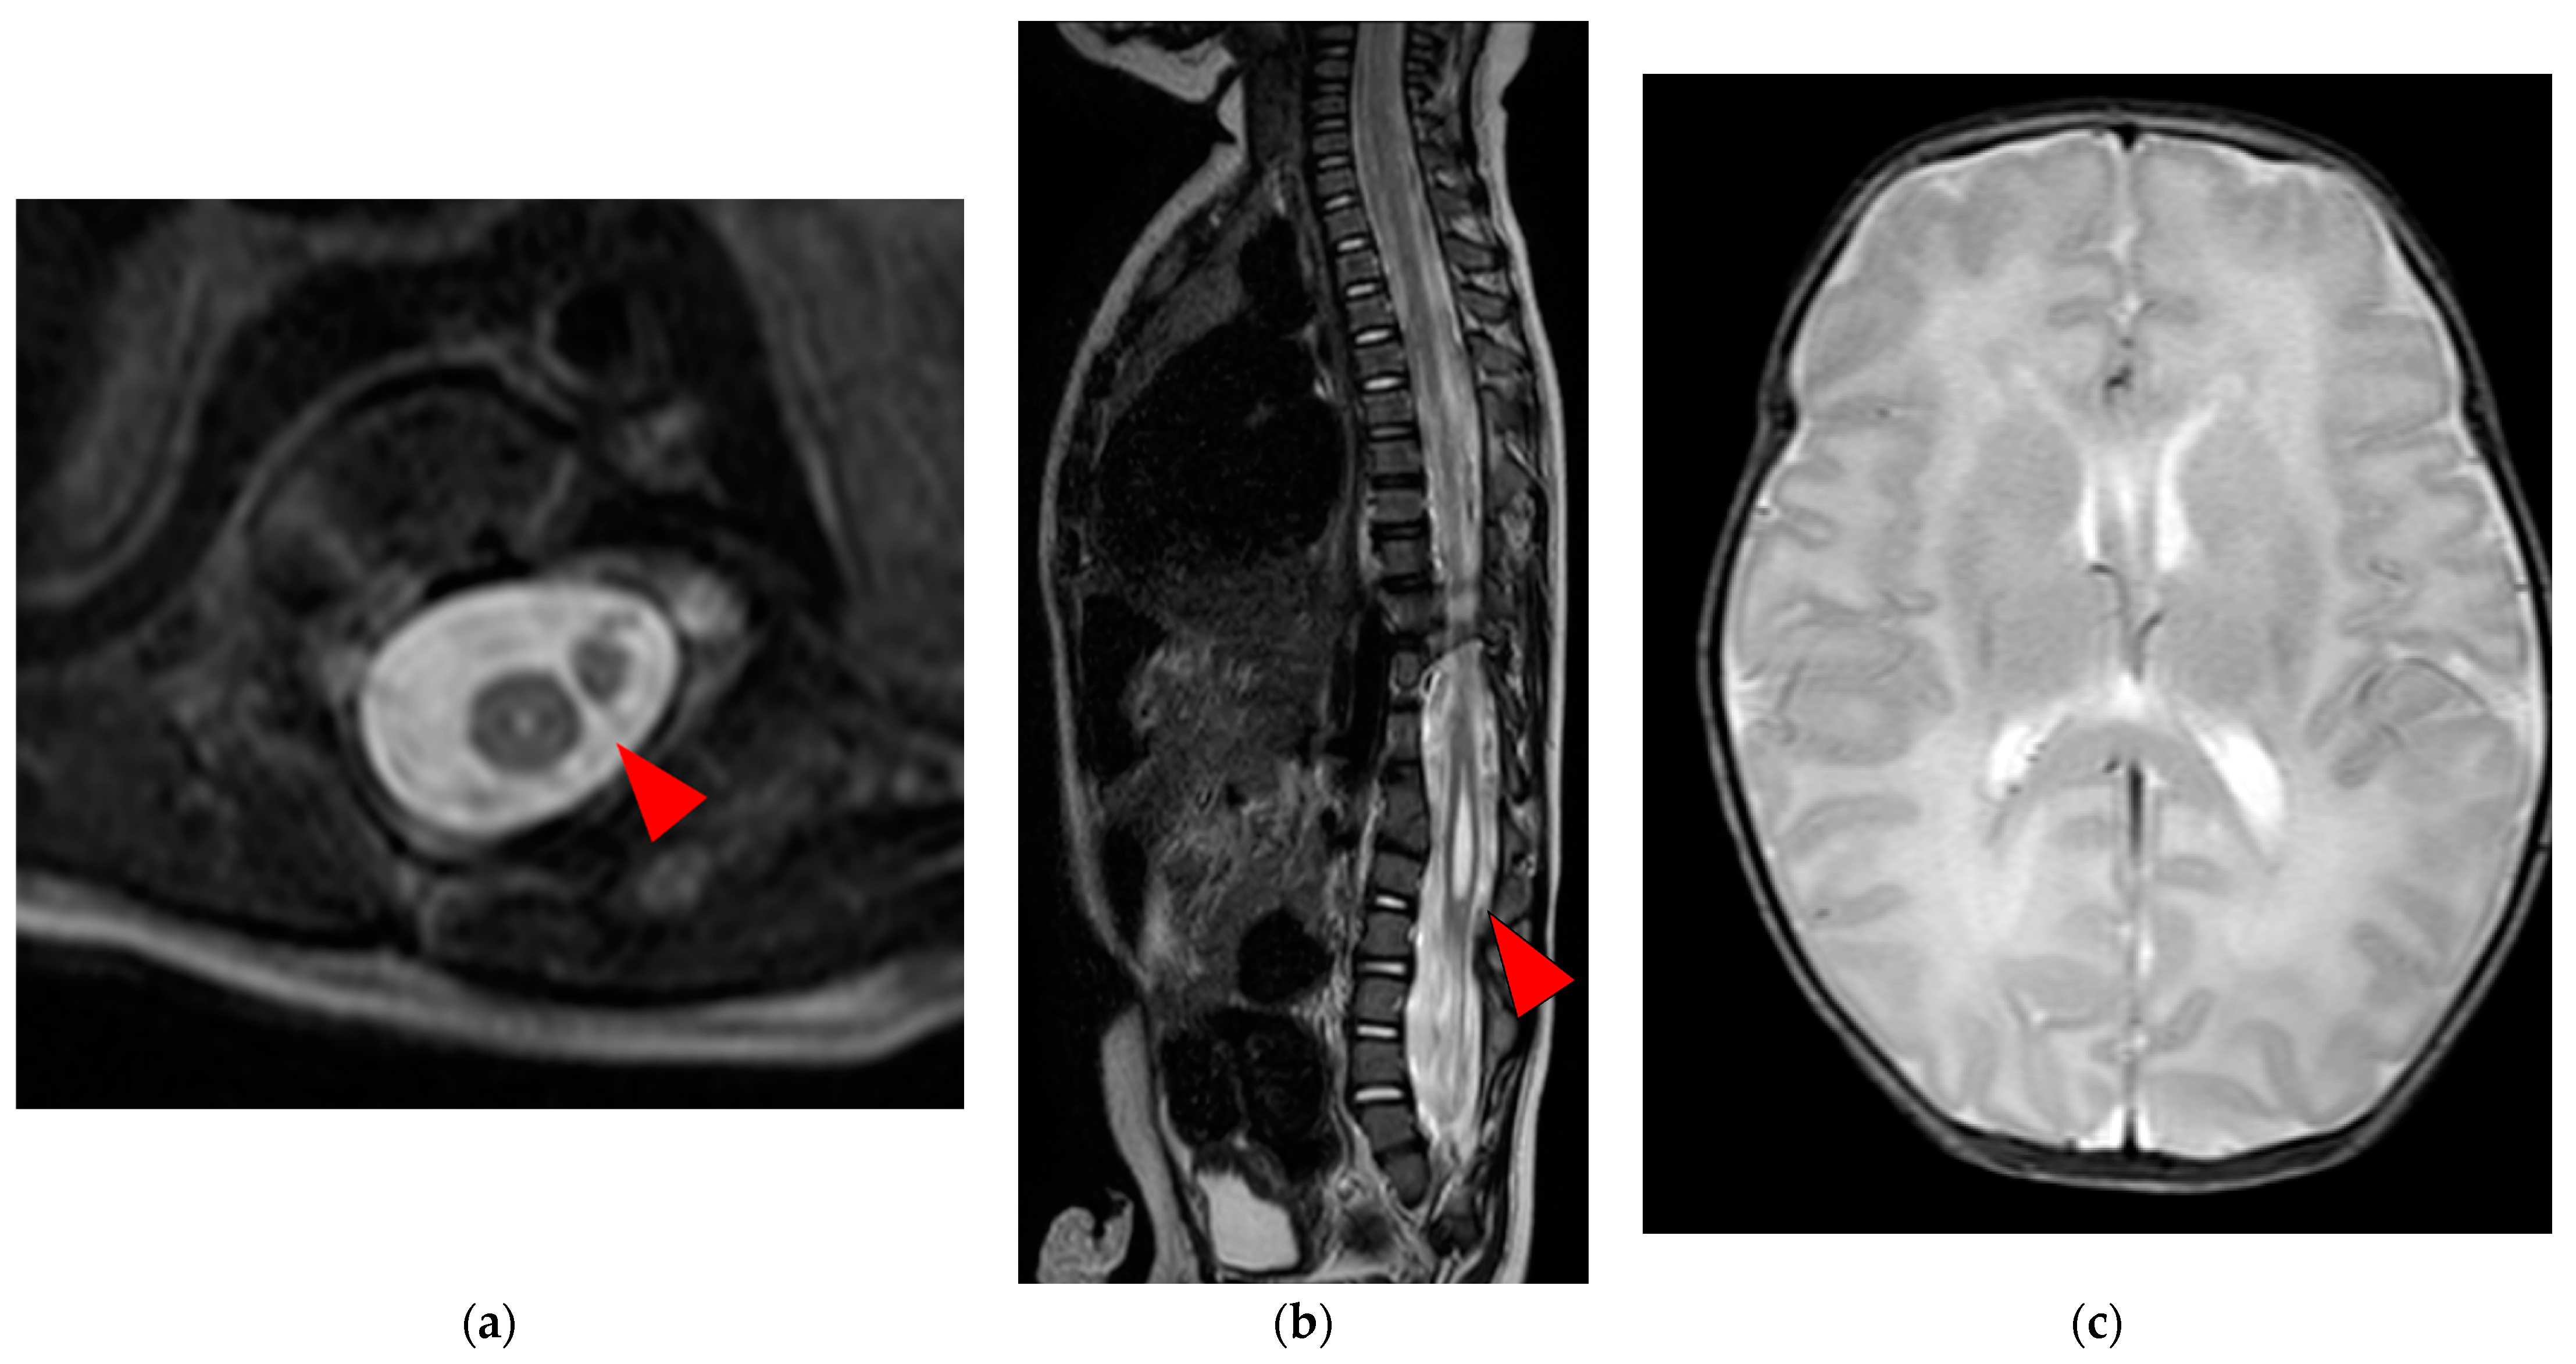

A Case of Neonate with Split Cord Malformation Presenting with Hypoplasia of the Left Lower Extremity

2. Case Report